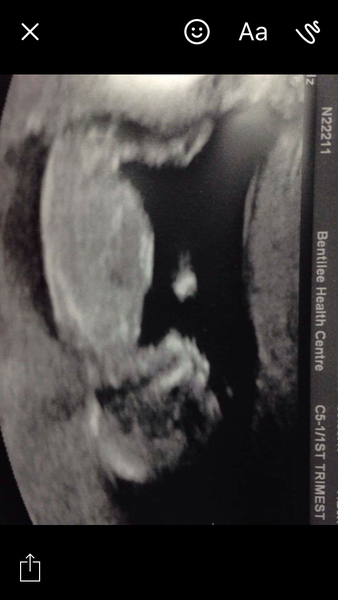

HannahJH · 02/03/2018 18:32

What about this one?